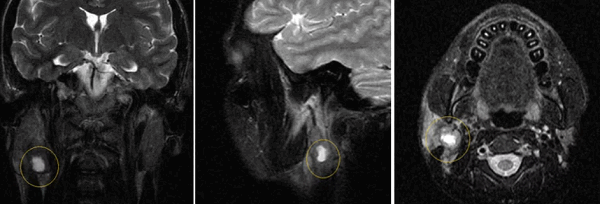

- Что такое аденома слюнной железы?

- Так называется доброкачественное образование в структуре железы. Аденома может возникать в больших и малых железах. Наиболее часто поражаются околоушные слюнные железы. Точные причины возникновения образований, в частности аденомы, на сегодня полностью не изучены. Основными теориями развития заболевания являются вирусное поражение, воспалительные изменения, травмы железы, вредные привычки (алкоголь и курение), несбалансированное питание. Аденома характеризуется медленным ростом и на начальных этапах может никак не проявлять себя.

Основными жалобами, при которых врач может заподозрить у пациента наличие аденомы слюнной железы, являются дискомфорт и неприятные ощущения в области железы, нарушение слюноотделения, болезненность в местах расположения крупных желез. Аденома слюнной железы хорошо видна на МРТ.

Аденома слюнной железы (Salivary gland tumor) — это доброкачественная опухоль, которая развивается из эпителия выводных протоков больших и малых слюнных желёз.

Опухоли слюнных желёз встречаются редко и в большинстве случаев они доброкачественные [9] . Чаще других доброкачественных опухолей развивается плеоморфная аденома (смешанная опухоль): в 70 - 80 % случаев, т. е. 2-3,5 случаях болезней слюнных желёз на 100 тыс. населения в год [6] [10] . Она может возникнуть в любом возрасте, но обычно развивается у людей от 20 до 49 лет. Мужчины и женщины болеют плеоморфной аденомой в соотношении 1,0:1,6 [1] [11] . Как правило, она развивается в околоушных, поднижнечелюстных и подъязычных железах. Часто поражает твёрдое и мягкое нёбо.

- КТ и МРТ — передают трёхмерное изображение слюнной железы и опухоли, что помогает точно определить её положение и размеры. Также с помощью МРТ можно узнать о строении опухоли, что сделает постановку диагноза более точной [1][2][3][4][5] .